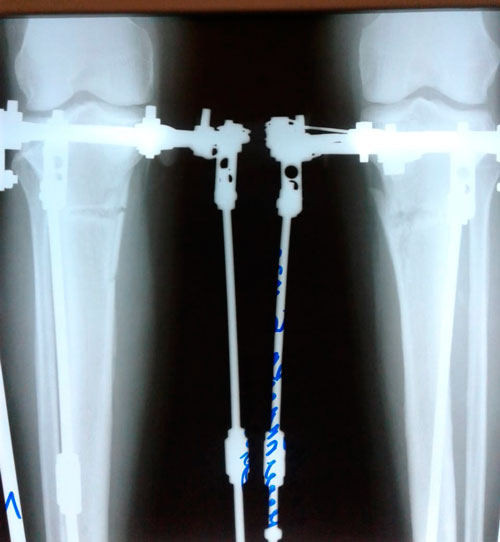

Дата операции - 05.03.2019г.

Дата снятия аппаратов - 26.06.2019г.

Срок сращения - 110 дней.